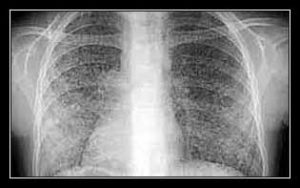

. Lao kê, những hạt nhỏ hình rải rác dồng nhất trong hai phổi;

BỆNH KÊ MẠN HOẶC BỆNH KÊ LẠNH:

- Bệnh bụi phổi: bệnh phổi nhiễm bụi silic, ngộ độc bêrili; trước tiên là hình ảnh liên quan đến các phần ở giữa và bên phổi.

- Bệnh sarcoit: thâm nhiễm hình nhiều nút không đồng nhất kèm với trung thất rộng, có hạch, phản ứng da âm tính; nếu cần, sinh thiết phế quản hoặc gan.